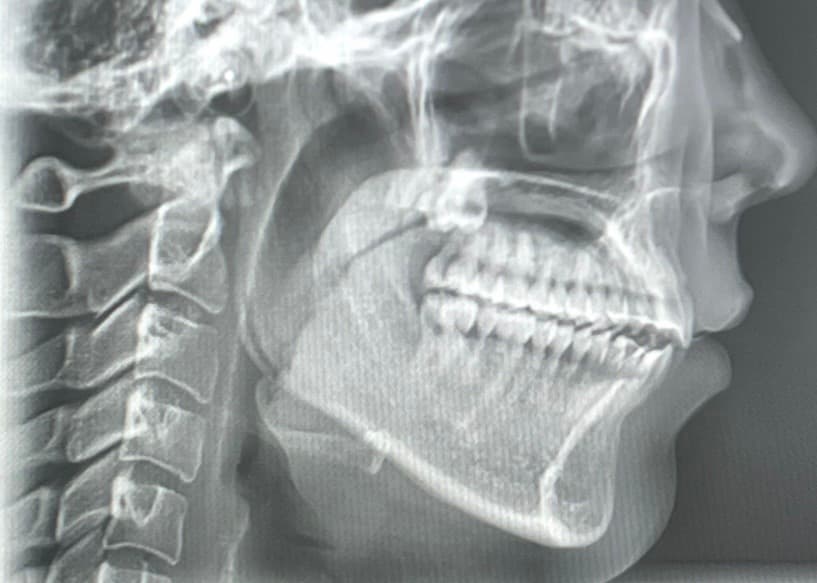

사진은 순서대로 턱 뒤로 회전하기 전,후입니다.

현재 엑스레이 사진상으론 어금니 교합은 정상적입니다. 치아 교합보다는 턱관절 문제에 집중해봐야 할 것 같습니다